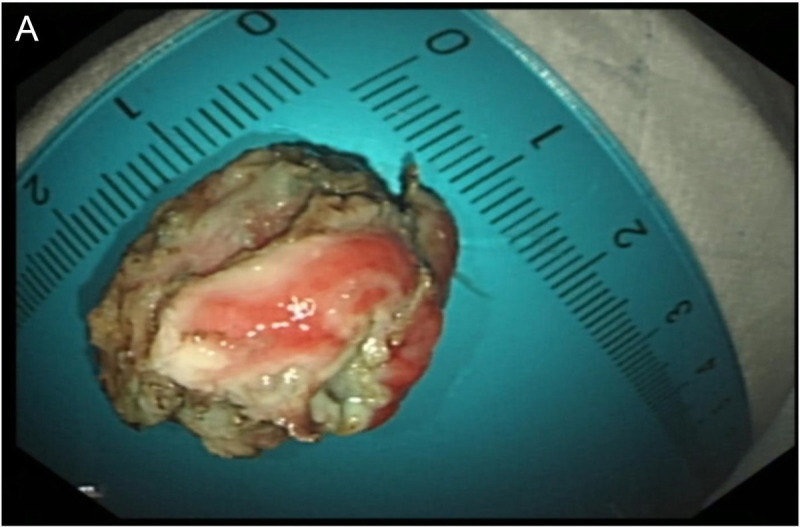

Intraductal papillary mucinous neoplasm originating from a heterotopic pancreas within the stomach.

起源于胃内异位胰腺的导管内乳头状粘液瘤。